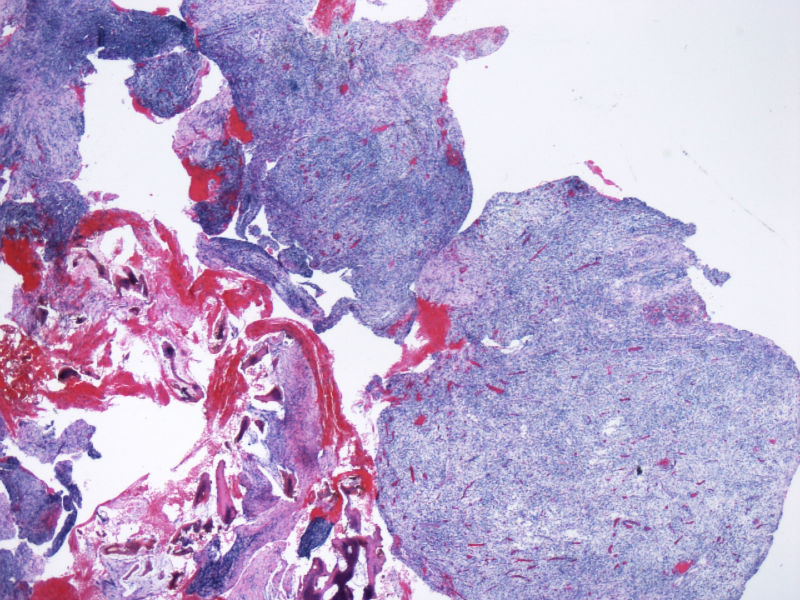

最终诊断为:ALK阳性的间变性大细胞淋巴瘤,淋巴组织细胞变异型。

拿出来的目的:本例始发于骨骼,临床提示脓肿或骨髓瘤,ALK阳性但EMA阴性,细胞毒只有一个标记阳性,本例CD4不阳性。因为CD30和CD15均有非肿瘤细胞阳性的情况,所以对于这个骨骼病例,细胞少而退变,因此最初没有信心诊断,但ALK一般不在非肿瘤细胞内阳性表达,所以最终还是诊断了ALCL。

ALK阳性ALCL发病年龄,发病部位,细胞形态可以非常广泛。西方国家统计男女比例为1.5:1,主要是40岁以内,尤其是儿童青少年多发。本例46岁女性,流行病学应少见的女性发病时段;

如金老师所言原发于骨也少见,如标题所显示:“临床骶骨脓肿?”表现为骨脓肿恐怕更少,综合以上所以本例的确特殊;

形态学hallmark 细胞显示不是很清晰,大的肿瘤细胞如果在ALCL和HL之间选择可能不容易,但HL的肿瘤细胞形态学特点的范围比较狭窄,而ALCL可能具有更广泛的形态学范围,细胞大小形态以及典型hallmark cell的多少有时很难确定。如果只看HE,觉得ALCL的可能会安全一点,当然我个人经验不足,可能理解得比较肤浅。